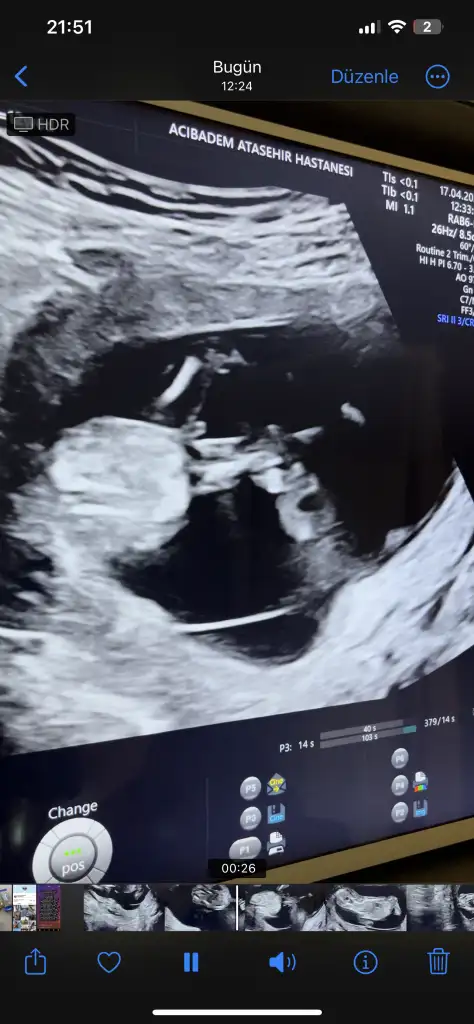

hıc anlasılır gelmedı bana :) dr ne dediBacak arası yorum sizde

Erkek dedihıc anlasılır gelmedı bana :) dr ne dedi

Senin Cinsiyet erkek miKocaman olmus..bakin bakalim cinsiyeti bilen var mi.bacaklari kapaliydi.. usg de anlayamayacaktik demek.dna testinde belli oldu.. su an ablam biliyor..benim.ogrenmem 1 ayi bulur sanirim... cenazemiz vardi..hemen kutlama yapamam . Annemde yok su an..onemi de yok aslinda..saglikli geldi ya sonuc. zaten benim her seyimi gec ogrendim